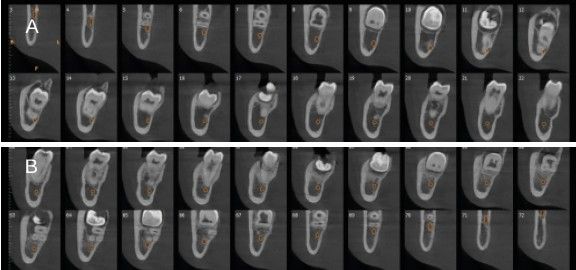

Métodos: Se presenta el caso clínico de un paciente varón de 18 años en el que, tras la realización de una CBCT de la arcada mandibular, se observó la retención de los segundos molares mandibulares permanentes junto con los terceros molares mandibulares.

Methods: We present the case of an 18-year-old male patient in whom, after performing a CBCT of the mandibular arch, retention of the permanent mandibular second molars was observed, along with the mandibular third molars.